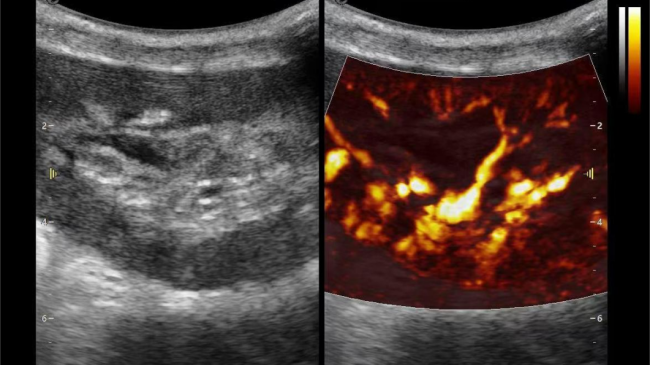

肾脏的灌注评估,RI/VI量化数据

超微视血流显像评估肾移植术后灌注情况

这一项无创、无辐射操作简便且无需造影剂的黑科技,相当于用"高速摄像机"记录血液细胞的运动轨迹,让血管并发症"无处遁形。

从术前评估到术中到术后,再到终身监护,当20-50μm级的超微血流信号在屏幕上跳动,我们看到的不仅是技术的精进,更是生命的律动。iPlane Vascular正在重新定义肾移植监护的标准——让医生拥有了"显微视力",让每一个微小血管的异常都无所遁形,让每一次免疫排斥的萌芽都被及时扼制。